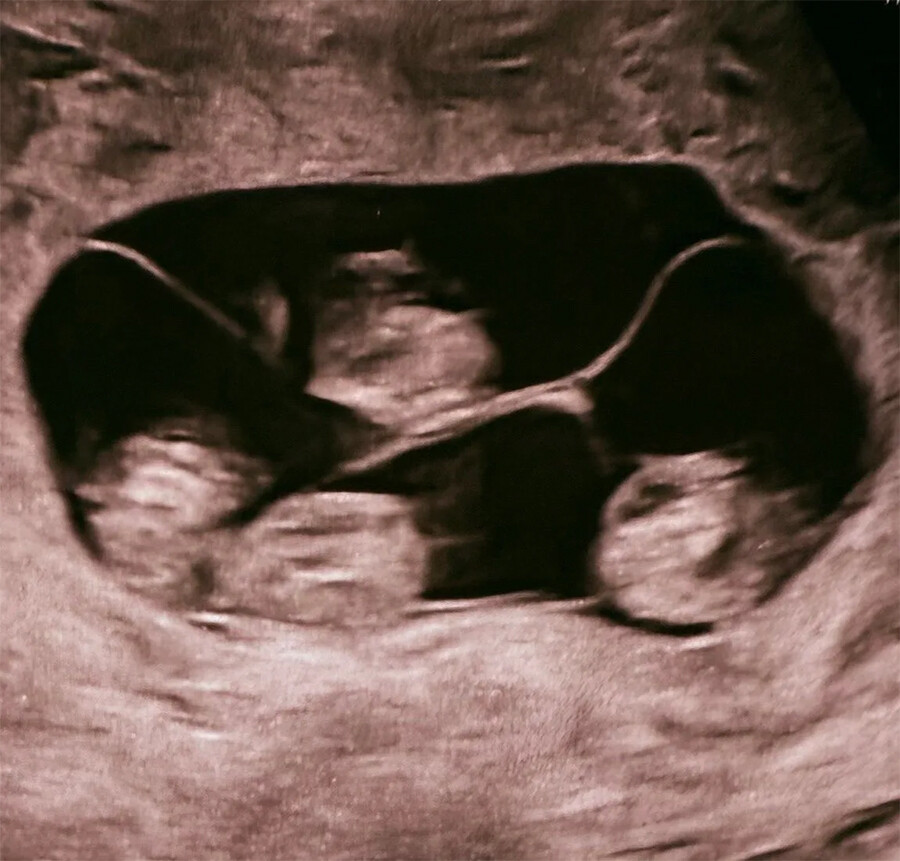

Однояйцевые четверняшки родились в роддоме № 17 в Санкт-Петербурге. Их появление на свет – это один случай на 15,5 миллиона родов, сообщили в медучреждении.

«Чудо в четвертой степени: в нашем роддоме родилась четверня! (...) На сроке 32 недели на свет появились четыре очаровательные сестренки. По расчетной статистике монохориальная - "однояйцевая" четверня – один случай на 15,5 миллиона родов. В стране не описано таких уникальных родов», – говорится в сообщении роддома в соцсети «ВКонтакте».

В медучреждении отметили, что каждого из четырех младенцев сразу после рождения принимали неонатологи и неонатальные сестры, чтобы обеспечить максимально бережный уход и поддержку с первых секунд жизни.